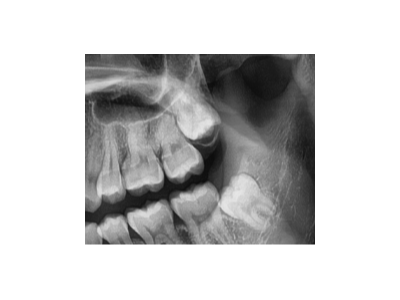

實際上,牙齒松動都是一個值得關(guān)注的口腔問題。那么,牙齒松動還能好嗎?答案是視情況而定。一、牙齒松動的原因牙周炎這是導(dǎo)致牙齒松動常見的原因之一。牙周炎是由牙菌斑中的細(xì)菌引起的慢性感染性疾病,會導(dǎo)致牙齦發(fā)…